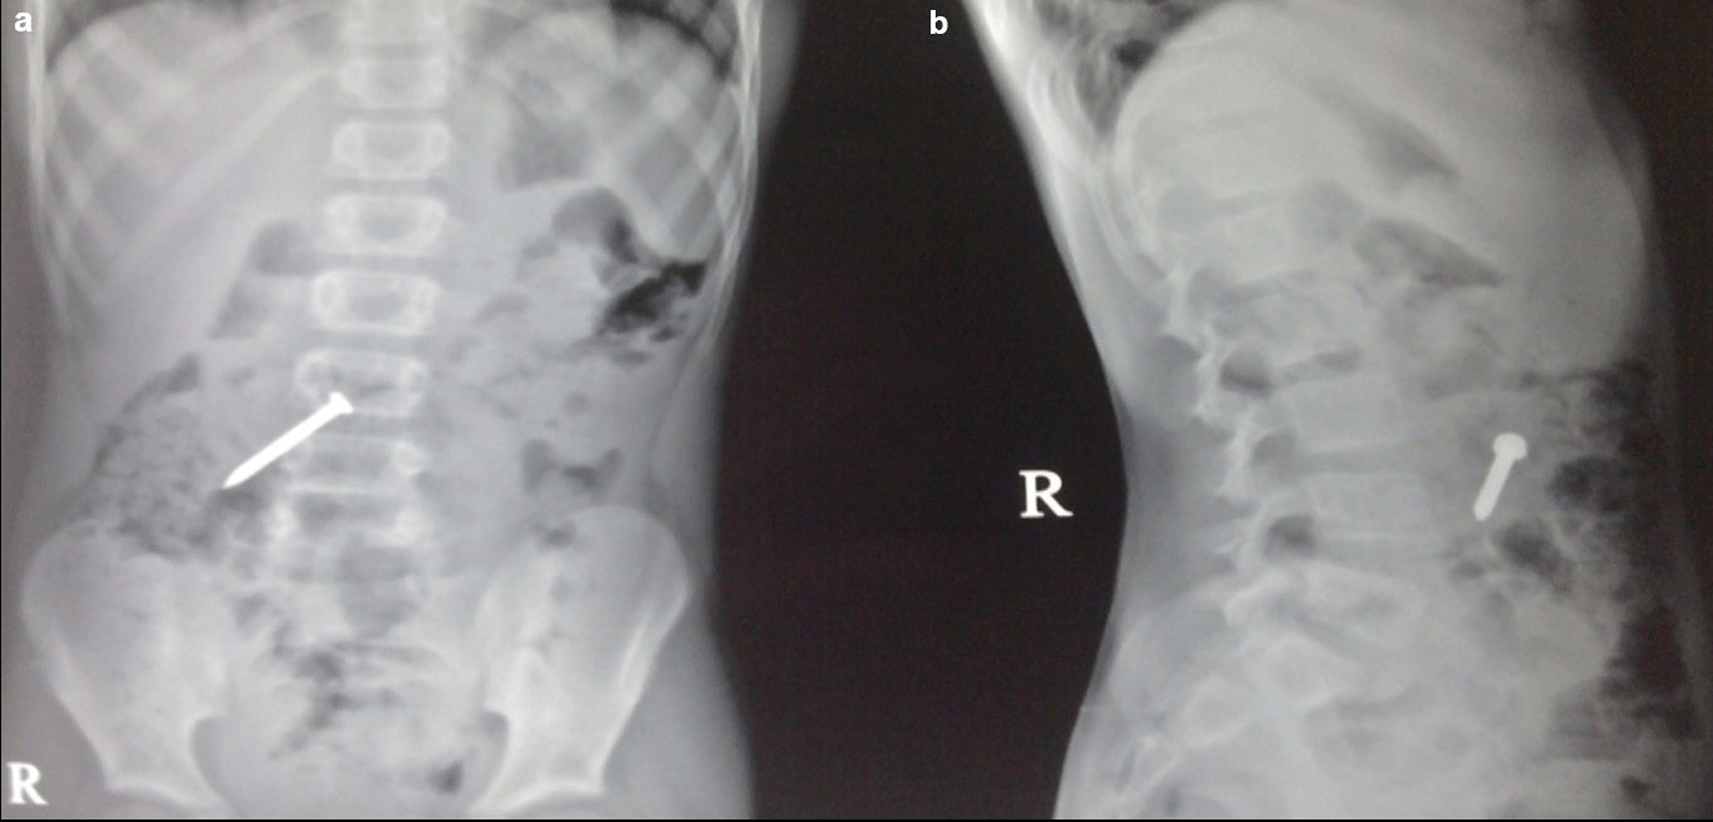

Case 2: A 34-year-old male carpenter by profession accidentally ingested a screw before 3 days. He had mild, intermittent pain in the right iliac fossa. The clinical examination revealed no significant findings. A radiograph of the abdomen in frontal and lateral views reveals a nail at the level of the L4 and L5 vertebrae in the gastrointestinal tract, which passed without any problems.

The swallowing of foreign bodies is a common condition in children and mentally challenged individuals.3–5 Fortunately, most ingested objects move through the digestive system without causing any problems (Figure 1a,b). Sharp and elongated objects can pass uneventfully (Figure 2a,b); however, they can pierce the mucosal lining and seriously damage or completely perforate the intestinal wall (Figure 3a-e). The object may just partially puncture the gut wall, resulting in a chronic inflammatory condition with few symptoms that is diagnosed months or years later.5–7